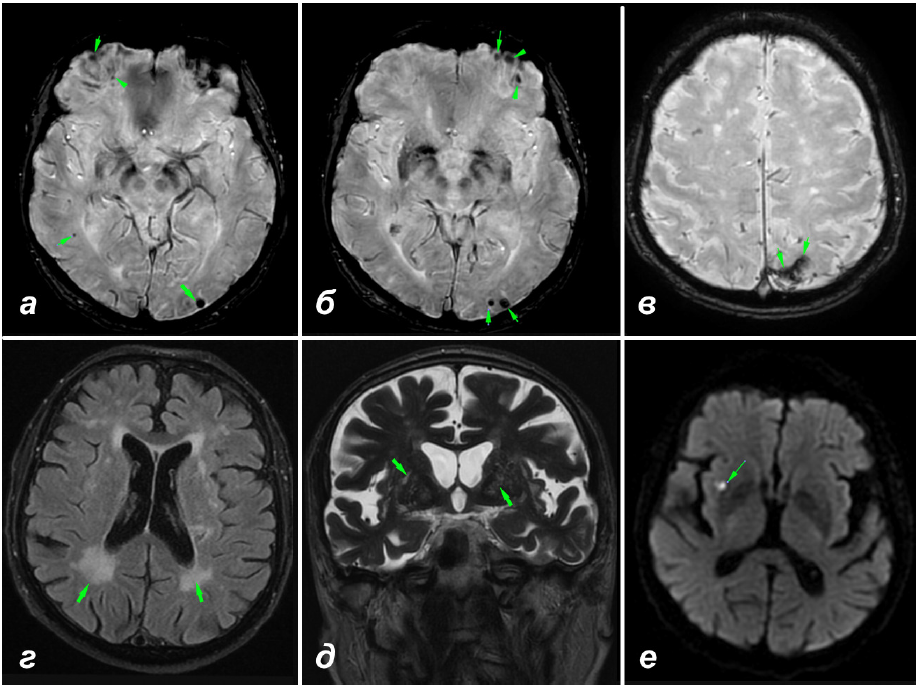

Рис. 2. Результаты нейровизуализации пациента Г.: а, б – множественные подкорковые долевые микрокровоизлияния (всего 8) (SWI); в – корковый поверхностный сидероз (SWI); г – преимущественно задний лейкоареоз (Fazekas 3) (FLAIR); д – МРТ-видимые периваскулярные пространства в области базальных ядер и полуовального центра (MacLullich 3); e – микроинфаркт в правой теменной доле (DWI)

По результатам кардиоваскулярного обследования выявлена гипертоническая болезнь. Зафиксировано резкое повышение ТТГ (26,6 мМЕд/л при норме до 4,0 мМЕд/л), расцененное эндокринологом как первичный гипотиреоз. Показатели общего и биохимического анализа крови, свертывания, а также концентрация витамина В12 и фолиевой кислоты в норме. По результатам МРТ выявлены признаки ЦБМС: ЦМК, КПС, задний лейкоареоз, расширение ПВП в области базальных ядер и полуовального центр, а также микроинфаркт (рис. 2). МРТ спинного мозга отклонений от нормы не выявила.

КПС как еще один ключевой геморрагический маркер ЦАА был описан относительно недавно [11]. Возникновение данного феномена связано с повторяющимися эпизодами просачивания крови в субарахноидальное пространство из пораженных ЦАА хрупких сосудов. Отложение гемосидерина в поверхностных слоях коры с каждой стороны извилины проявляется характерным паттерном выпадения сигнала на Т2*- и SWI-последова тельностях МРТ в виде двух дорожек. КПС может быть подразделен на фокальный (распространяется не более чем на 3 борозды) и диссеминированный (4 борозды и более) [2]. У представленного пациента наблюдается фокальный КПС в затылочной доле, отчетливо визуализированный в режиме SWI (см. рис. 2, в).

Встречаемость КПС у лиц 60 лет и старше без деменции составляет 0,7 %, что значительно ниже распространенности ЦМК (14 %). Для пациентов с КПС типично также наличие долевых ЦМК, по крайней мере одно из которых расположено вблизи участка КПС [19]. Аналогичная картина наблюдается в приведенном случае: у пациента обнаружены 8 ЦМК, два из которых расположены в левой затылочной доле, рядом с участком КПС. Тем не менее все больше данных появляется в пользу того, что КПС может не сопровождаться ЦМК (в 6–54 % случаев) и являться единственным маркером ЦАА [2].

Наличие у пациента Г. КПС, множественных ЦМК и расширение ПВП в области полуовального центра позволило заподозрить ЦАА. При оценке нейровизуализационной картины по бостонским критериям установлен диагноз вероятной ЦАА (множественные кровоизлияния ЦМК, ограниченные долями мозга, корковыми или корково-подкорковыми зонами, и фокальный КПС в отсутствие других причин кровоизлияний, возраст пациента 83 г.). Спорным остается вопрос о природе эпизодов остро возникающего двоения в глазах у данного пациента. С одной стороны, их характеристика не укладывается в классическое описание ТФНЭ: длительность обоих эпизодов составляла несколько дней (вместо типичных для ТФНЭ нескольких минут – часов), ТНФЭ, проявляющихся диплопией, в изученной литературе не описано, более типичным их проявлением являются парестезии и парезы. Однако ввиду недостаточной изученности проблемы, стереотипности клинических проявлений (второй эпизод со схожей клиникой без явного морфологического субстрата) и расположения КПС в затылочной доле в данном случае эпизоды диплопии теоретически могут быть расценены как ТНФЭ. При этом нельзя с полной уверенностью говорить о том, что описанные пациентом эпизоды действительно были диплопией, а не метаморфопсией.